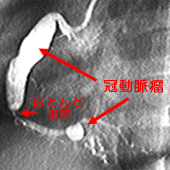

川崎病の原因はわかっていませんが、要は全身の血管が腫れる病気です。いろいろな症状はすべて血管が腫れるために起こるのです。一番やっかいな腫れる場所、これが冠動脈なのです。

川崎病にかかると、これら、成人病にしか登場してこない、命取りになる大事な大事な場所に、病気ができてしまうことがあるのです。

具体的には、こぶができるのですが、こぶ自体が破裂したりすることはほとんどありません。しかし、こぶが治っていくとき、ギザギザ・デコボコに治って、狭いところを作ってしまうことがあるのです。

川崎病に100人かかったとして、一時的に冠動脈がちょっと腫れる人は、30-50人ほどいますが、冠動脈瘤としてできあがってしまう人は、10人くらい。そのうち中がギザギザになって、心筋梗塞を起こしたりする人は1人くらいの頻度です。